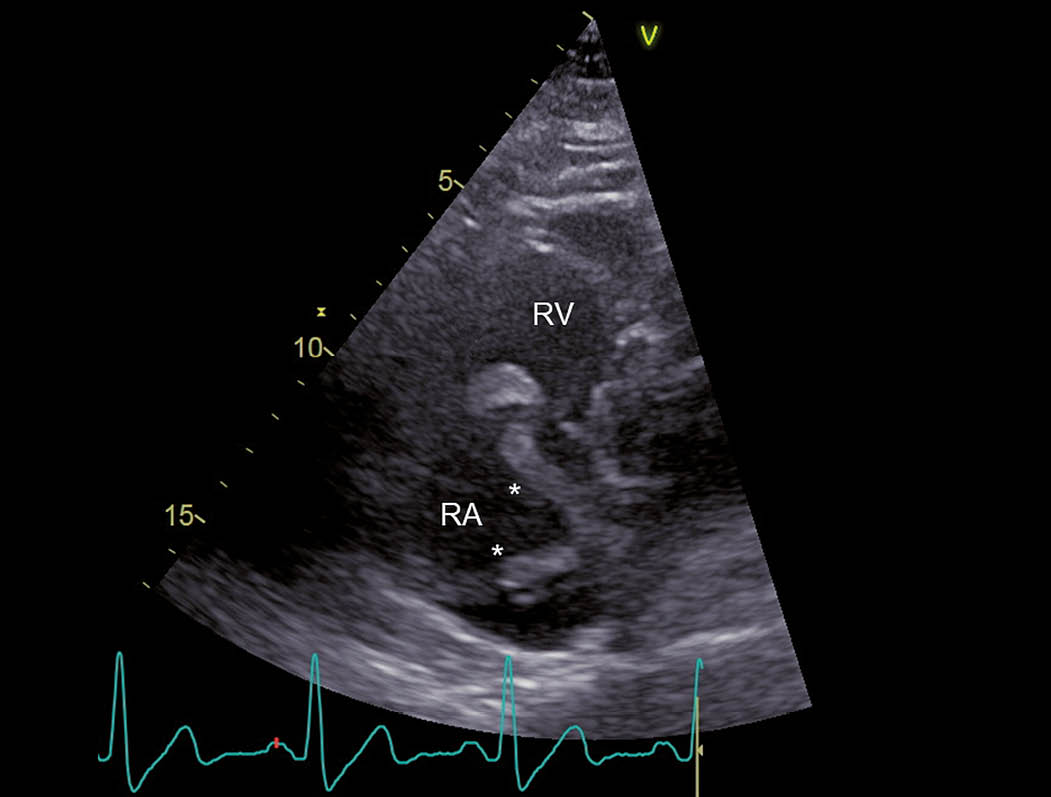

Abb. 3: RV-modifizierter apikaler Vierkammerblick Im rechten Atrium zeigt sich ein grosser, zweischenkliger Thrombus (*), welcher am interatrialen Septum adhärent zu sein scheint (Pfeil). RV = rechter Ventrikel und RA = rechtes Atrium.

Abb. 4: RV-modifizierter apikaler Vierkammerblick Erneute Darstellung des grossen rechtsatrialen Thrombus (*), wobei in diesem Bild der grössere der beiden Schenkel durch die Trikuspidalklappe in den rechten Ventrikel prolabiert (Pfeil). RV = rechter Ventrikel und RA = rechtes Atrium.